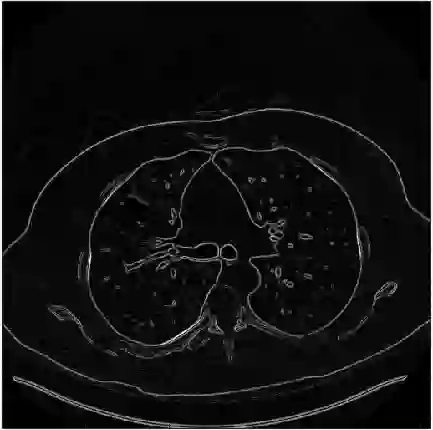

In this work, we present Eformer - Edge enhancement based transformer, a novel architecture that builds an encoder-decoder network using transformer blocks for medical image denoising. Non-overlapping window-based self-attention is used in the transformer block that reduces computational requirements. This work further incorporates learnable Sobel-Feldman operators to enhance edges in the image and propose an effective way to concatenate them in the intermediate layers of our architecture. The experimental analysis is conducted by comparing deterministic learning and residual learning for the task of medical image denoising. To defend the effectiveness of our approach, our model is evaluated on the AAPM-Mayo Clinic Low-Dose CT Grand Challenge Dataset and achieves state-of-the-art performance, $i.e.$, 43.487 PSNR, 0.0067 RMSE, and 0.9861 SSIM. We believe that our work will encourage more research in transformer-based architectures for medical image denoising using residual learning.